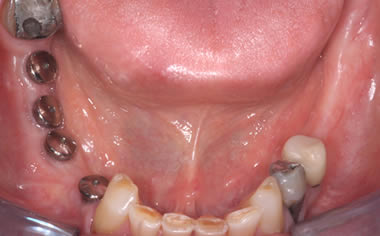

More back teeth replaced by dental implants

Case Five (4 images)